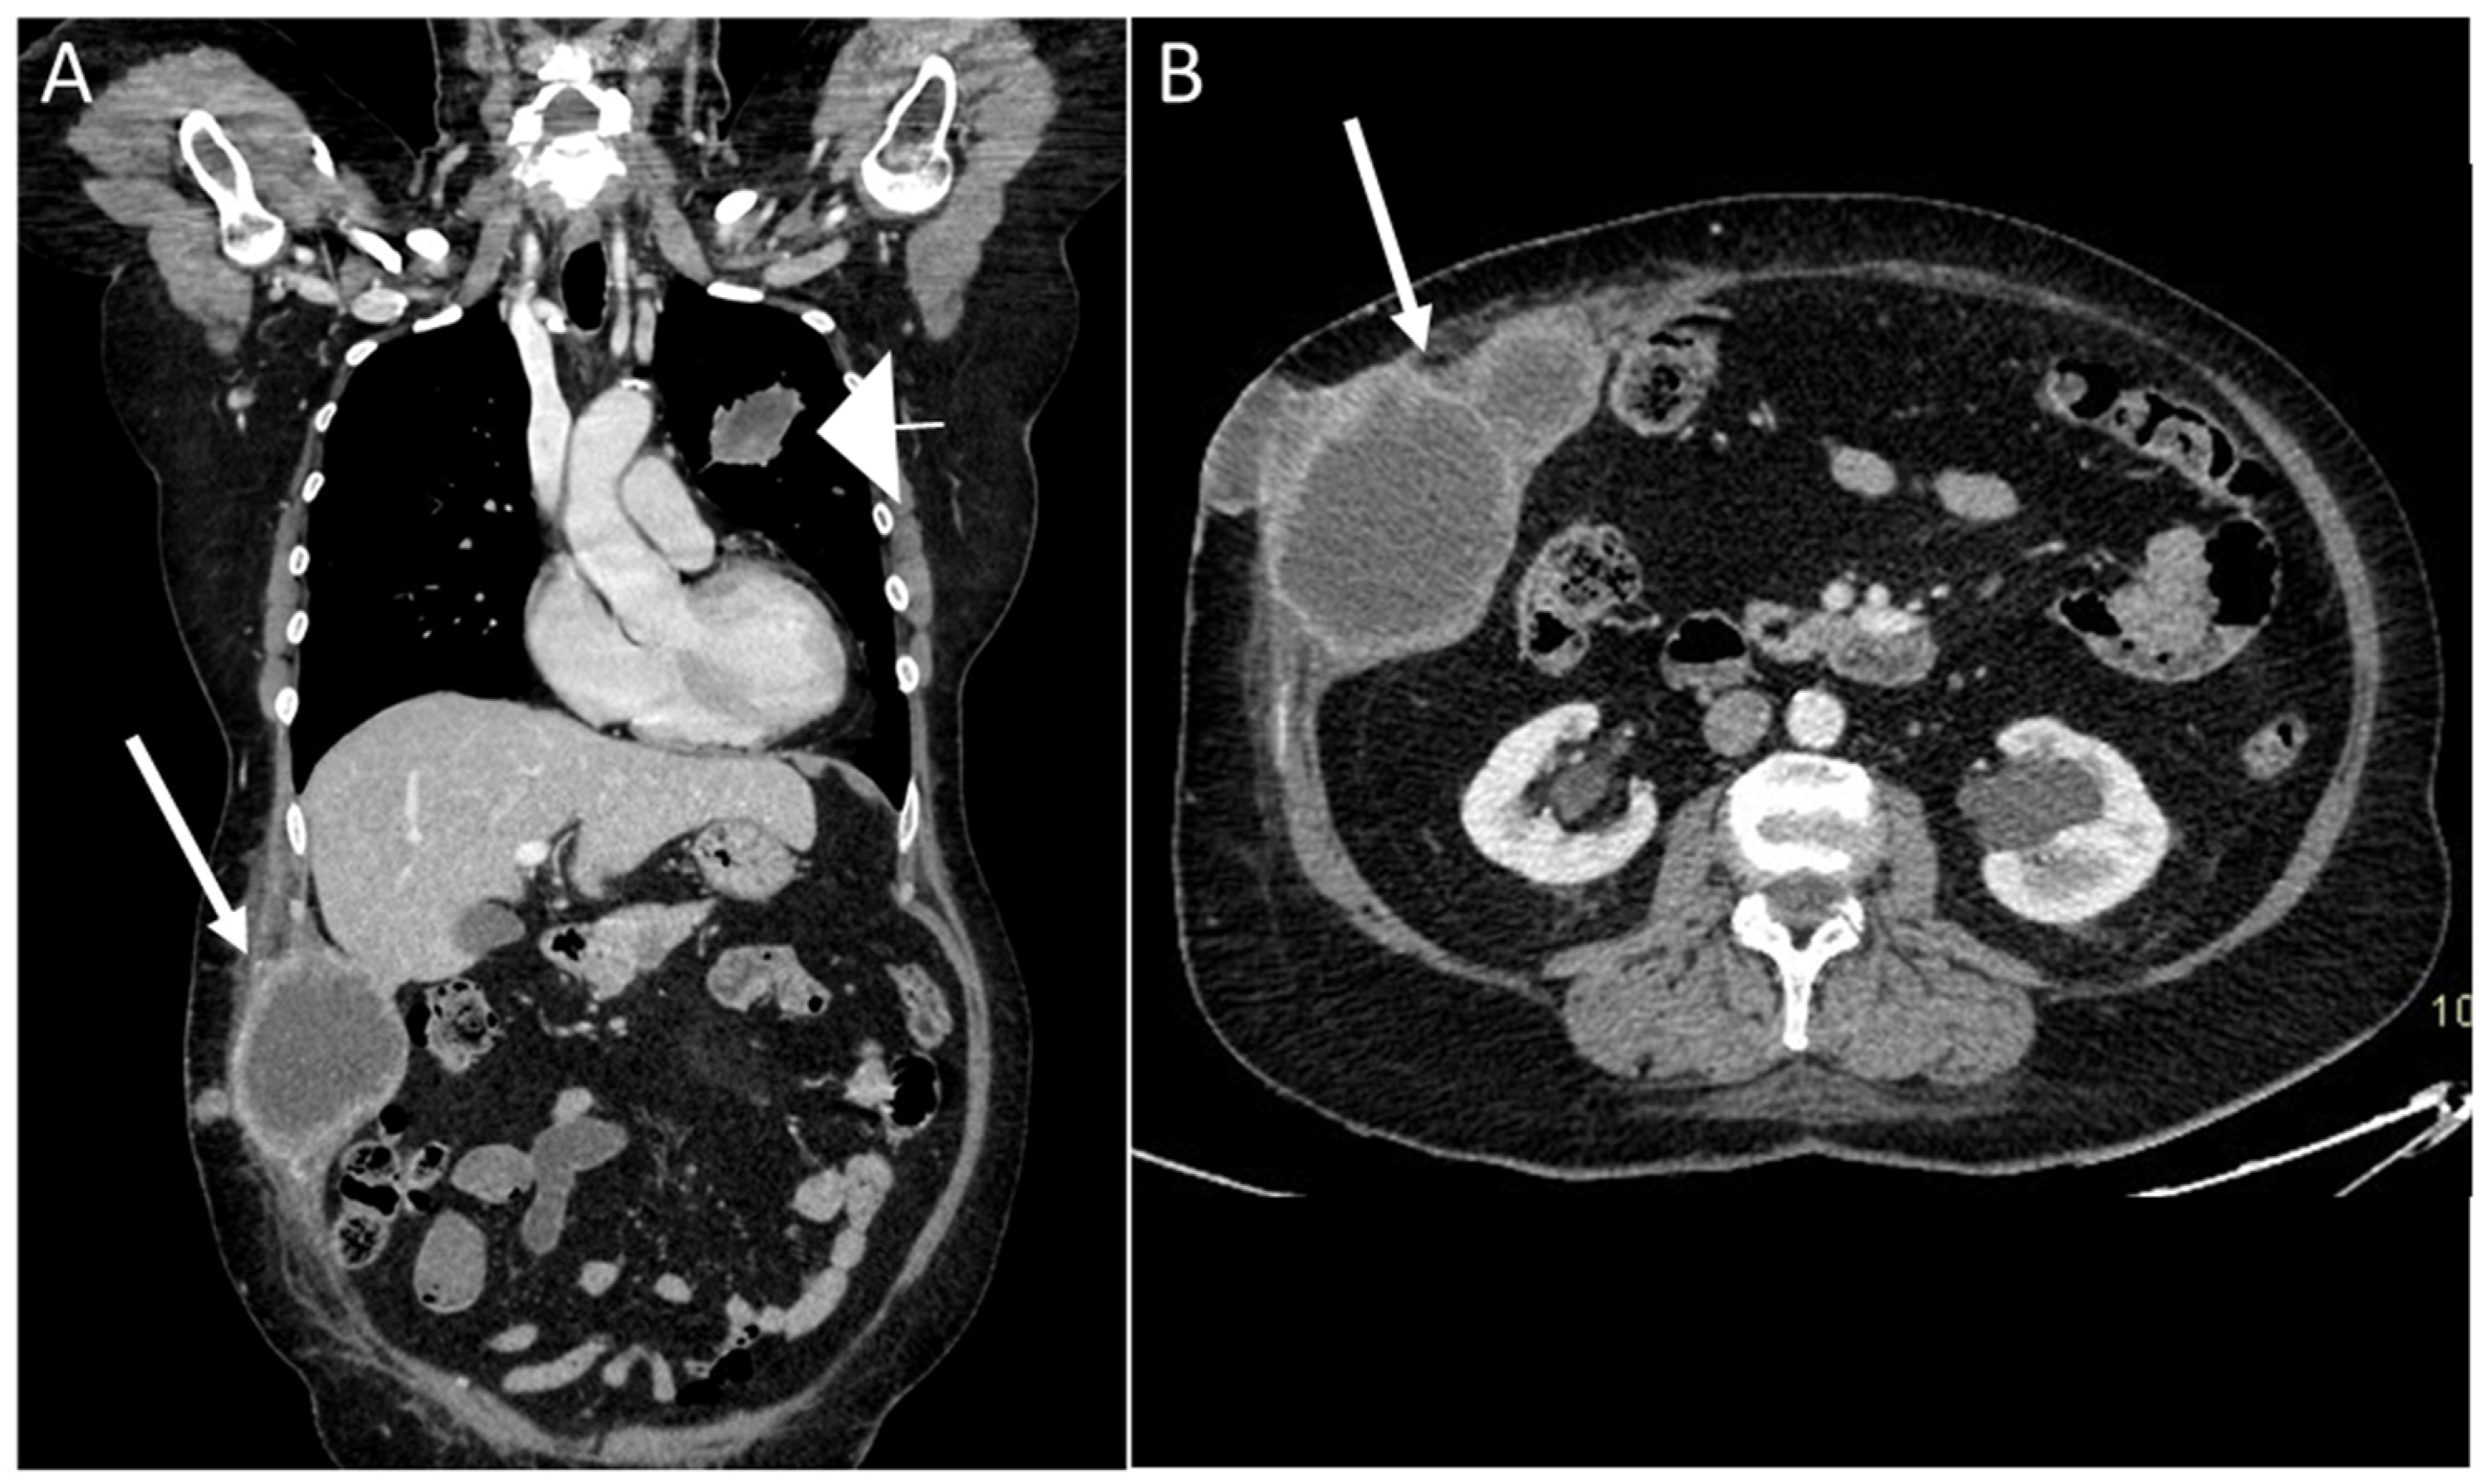

- Gastrointestinal Stromal Tumors (GIST): either primary (extraintestinal GIST, “EGIST”) [25,26] or secondary GIST of the abdominal wall are rare. When extended (>5 cm), GIST may have an aggressive behavior [25]. CT is the imaging modality of choice, showing heterogeneous vivid enhancement, and variable amount of necrosis. Peculiar findings include calcifications and cystic degeneration [27,28,29].